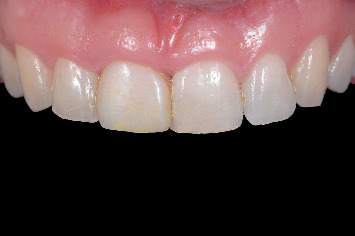

简介:当用种植体替换美学区单个牙齿时,对于大面积颊骨缺损的病例,保留牙槽嵴是必要的。假体驱动种植体放置在保留的脊上,随后立即进行患者特定的临时修复,可以通过数字治疗计划实现。数字化工作流程结合了口腔内光学扫描和锥形束计算机断层扫描,实现了三维临床和放射学解剖评估。此外,它通过计算机辅助手术和CAD/CAM钛基台的临时修复预制,促进了完全引导的种植体放置。材料与方法:对3例上颌美观区缺牙及颊骨缺损bbbb5 mm的患者行牙槽嵴保存术。四个月后,使用数字工作流程放置种植体,并使用患者特定的钛基台进行预制临时修复。3个月后进行了最终修复。在治疗前、临时修复后6周、最终修复后1个月和1年评估临床、美学、放射学和患者报告的结果。结果:3例患者在牙槽嵴保存后伤口愈合良好,种植体可按计划放置并临时修复。在最后的随访中,观察到健康的种植体周围组织,美观性好,患者满意度高。结论:三个报告的病例展示了数字工作流程在上颌美学区保留脊中使用预制修复体进行延迟种植体放置的潜力。

Introduction: When replacing a single tooth in the aesthetic zone with an implant, alveolar ridge preservation is necessary in cases with extensive buccal bone defects. Prosthetically driven implant placement in the preserved ridge, followed by an immediate patient-specific temporary restoration, can be achieved with digital treatment planning. A digital workflow incorporates intraoral optical scanning and cone beam computed tomography, enabling a three-dimensional clinical and radiographic anatomy assessment. Furthermore, it facilitates fully guided implant placement by means of computer-assisted surgery and the prefabrication of temporary restorations with a CAD/CAM titanium abutment. Materials and Methods: Three patients with a failing tooth in the maxillary aesthetic zone and a buccal bone defect > 5 mm underwent alveolar ridge preservation. Four months later, a digital workflow was used to place the implant, which was restored with a prefabricated temporary restoration with a patient-specific titanium abutment. The definitive restoration was placed 3 months later. Clinical, aesthetic, radiographic, and patient-reported outcomes were assessed before treatment, 6 weeks after temporary restoration, and 1 month and 1 year following definitive restoration. Results: In all three cases, wound healing after alveolar ridge preservation was uneventful, and the implants could be placed and restored with a temporary restoration, as planned. At the final follow-up, healthy peri-implant tissues were observed with good aesthetics and high patient satisfaction. Conclusion: The three reported cases demonstrate the potential of a digital workflow for delayed implant placement with provisionalization using prefabricated restorations in preserved ridges within the maxillary aesthetic zone.